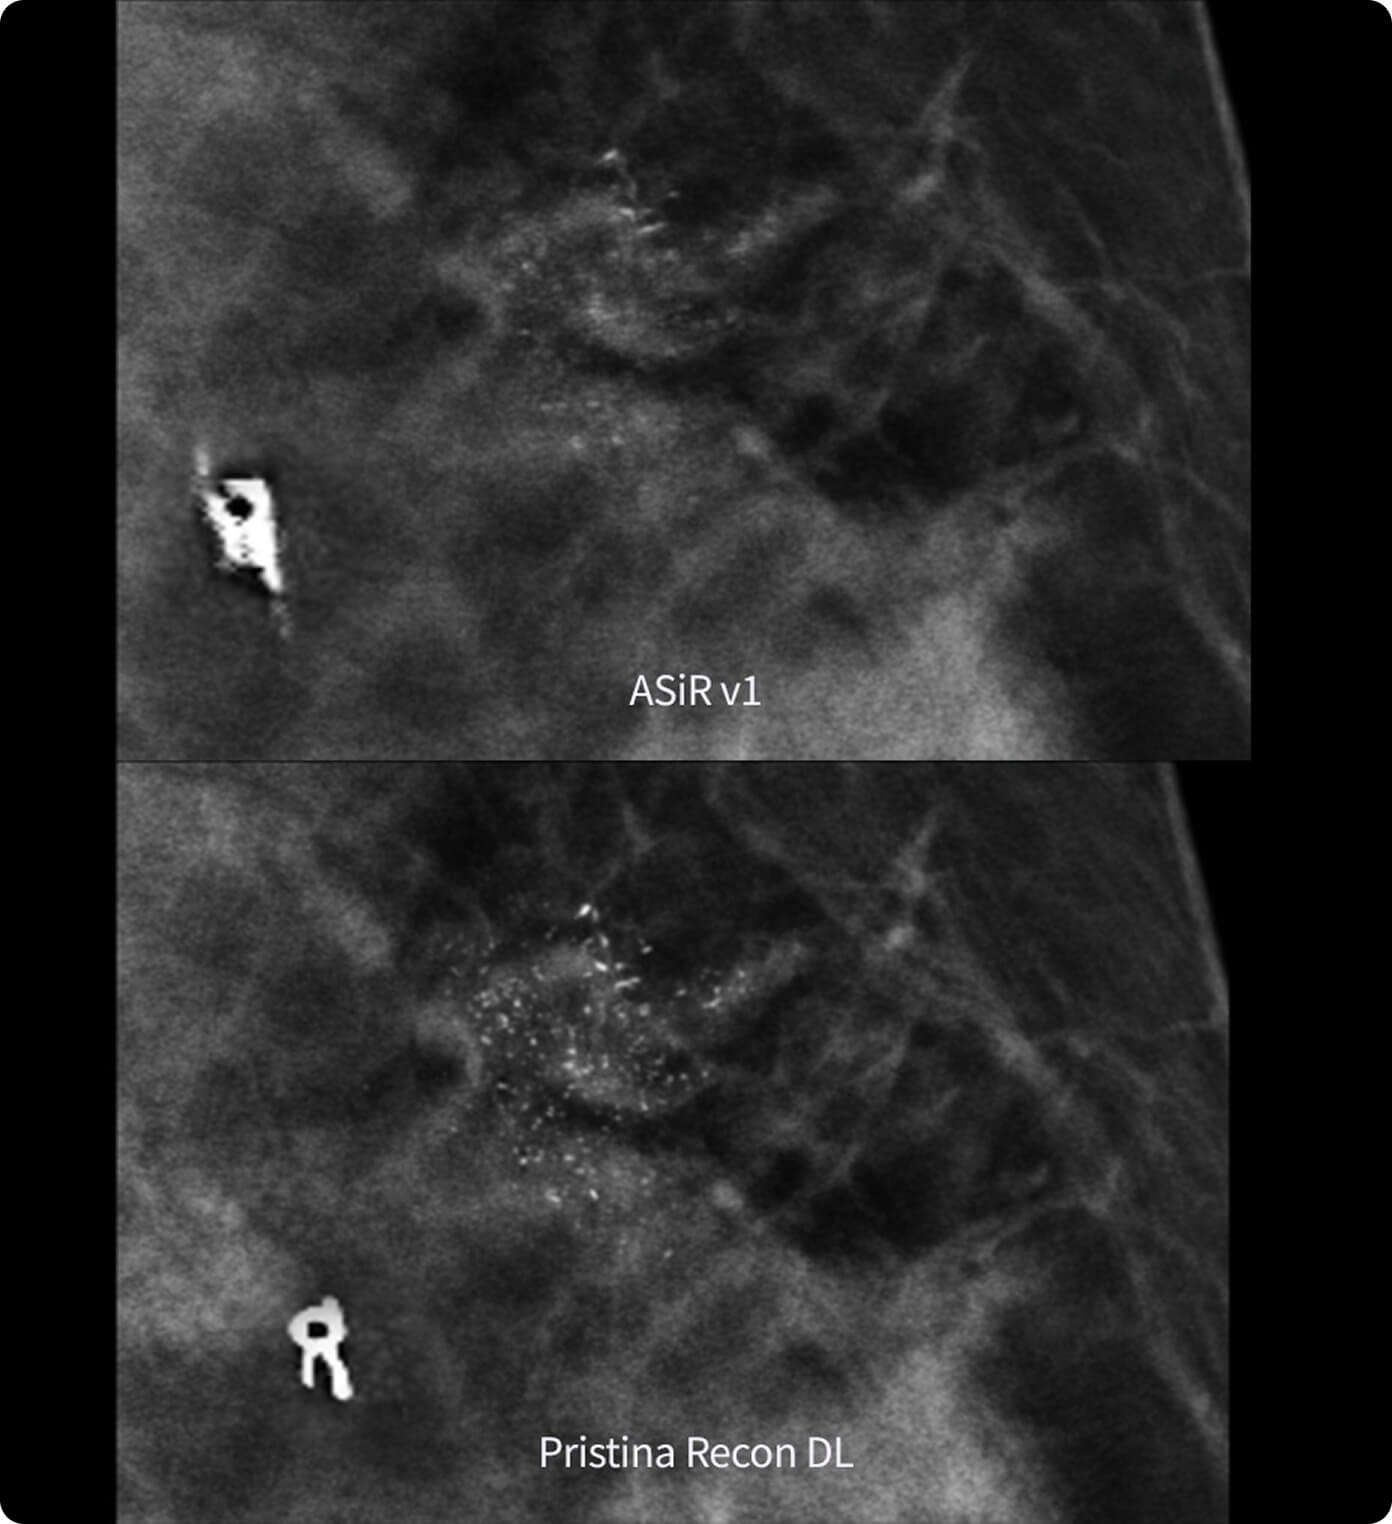

Shadow Reduction

Confident answers